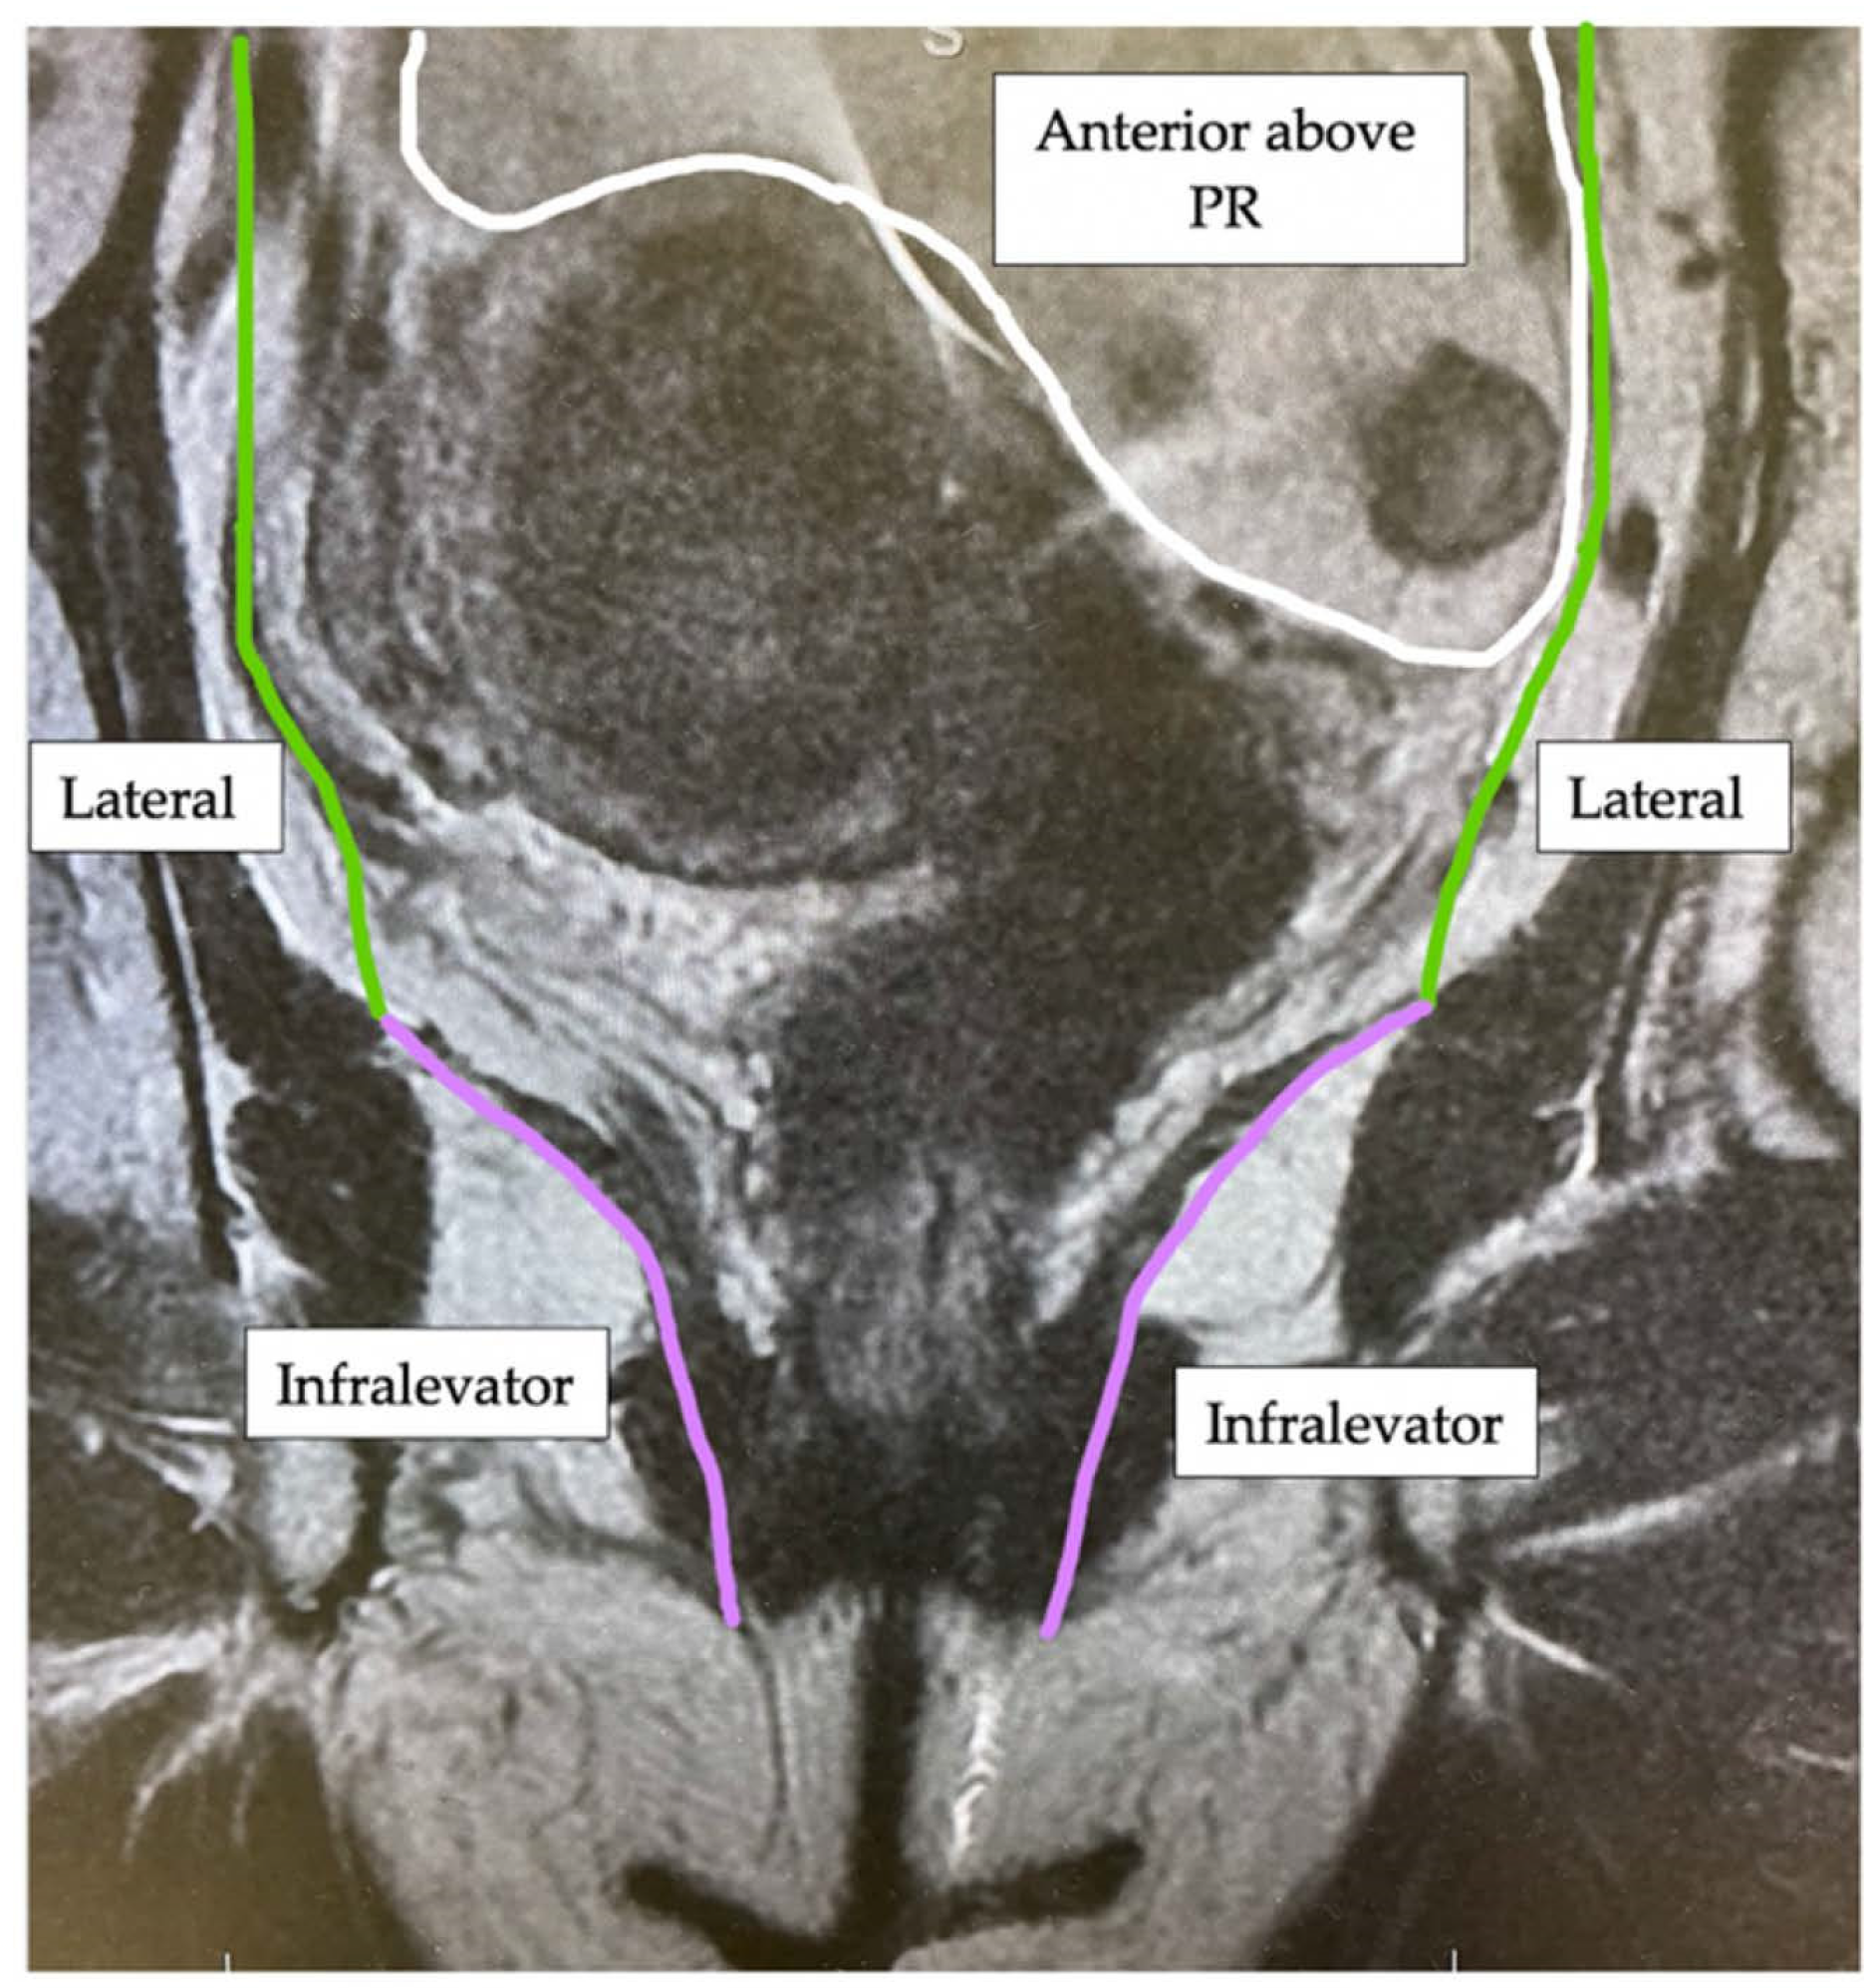

| Compartment | Structures within Compartment |

|---|---|

| Anterior above Peritoneal Reflection | Ureters, iliac vessels above peritoneal reflection, sigmoid colon, small bowel, lateral pelvic sidewall fascia (peritoneal surface) |

| Lateral | Internal and external iliac vessels, lateral pelvic lymph nodes, piriformis muscle, internal obturator muscle |

| Infralevator | Levator ani muscles, external sphincter complex, ischio-anal fossa |